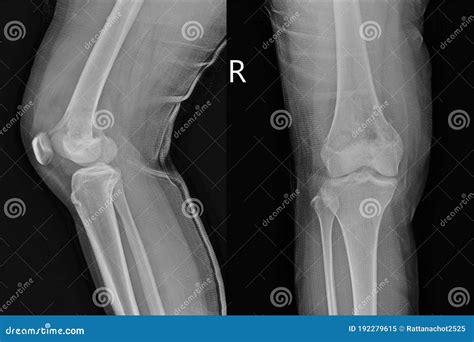

Radiographic imaging acts as a gateway to further diagnostic procedures, such as biopsies and MRI scans. When a physician suspects a bone tumor, an Osteosarcoma X Ray is ordered to evaluate the integrity of the bone, the extent of tumor involvement, and the relationship between the tumor and surrounding soft tissues.

The primary goal of the initial X-ray is to assess for "aggressive" features that distinguish a potentially malignant tumor from a benign one. Radiologists look for specific patterns of bone destruction and the body’s reaction to the lesion. While these imaging findings can be highly suggestive, they must always be correlated with the patient's clinical history, physical examination, and subsequent pathological analysis.

When reviewing an Osteosarcoma X Ray, radiologists and clinicians do not work in isolation. The imaging findings are only as valuable as the clinical story behind them. A high index of suspicion is required when the patient—most commonly an adolescent experiencing a growth spurt—reports localized, persistent pain, swelling, or a reduced range of motion in a joint, particularly around the knee (the distal femur or proximal tibia).

Sometimes, patients attribute this pain to a sports injury or "growing pains," which can lead to a delay in obtaining imaging. If pain does not subside with standard treatment, rest, or over-the-counter anti-inflammatory medications, it is imperative to seek professional medical advice. The X-ray is the essential tool that can quickly turn a vague complaint of "knee pain" into a prioritized, actionable medical investigation.